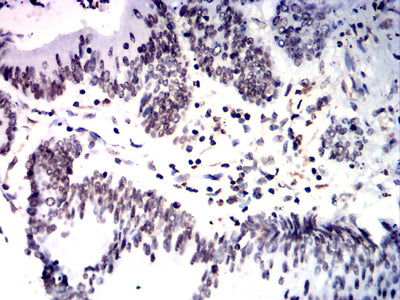

分类: 科研抗体货号: 32344别名: SS1; DRB1; HLA-DRB; HLA-DR1B应用: IHC,FCM反应种属: Human